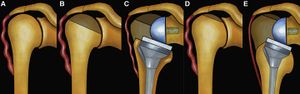

The glenosphere has to be implanted on the lower part of the glenoid to avoid notching and to improve rotation at 90 degrees of abduction.[23][24][25][18][26][27] The type of glenosphere (size, eccentricity) allowed the adjustment of arm length by several millimeters (about 1% of arm length). Consequently, the key factors for arm length are the height of the stem, type of stem, polyethylene thickness and the use of an augment or spacer. Collectively, these factors allow arm lengthening by up to several centimeters (about 10% of arm length).[19] The tension is thus determined by arm length. The latter is dependent of 1) the position of the glenosphere in the frontal plane (Figure), 2) the size of the glenosphere, 3) the use of an eccentric or inferiorly tilted glenosphere, 4) the use of a spacer, 5) the thickness of the polyethylene, 6) the height of humeral cut and stem implantation (Figure 3)[28] and prosthetic design (Figure).

Influence of position of glenosphere in vertical plane. (A) A rather high implantation of the baseplate or the use of a non-eccentric glenosphere does not allow proper deltoid re-tensioning. (B) The use of an eccentric glenosphere or a low position of the glenosphere in the vertical plane allows satisfactory deltoid re-tensioning,[28] with permission

Influence of the humeral cut on arm length. (A) Preoperative status with a lack of deltoid tension. (B-C) An aggressive humeral cut results in a low implantation of the stem with a lack of deltoid tension. (D-E) A minimal humeral cut leads to a high implantation of the prosthetic stem with adequate deltoid tension. From: Lädermann et al., with permission,[28] with permission